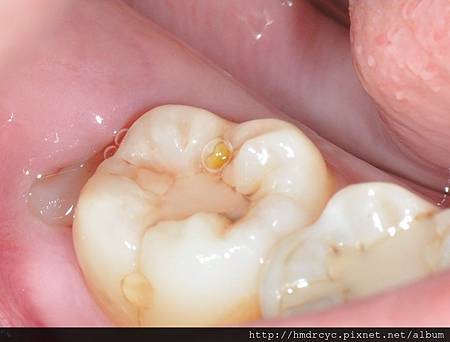

當智齒長歪頂到前面的牙齒

細菌跑進來的時候會無法清潔

頂到前面牙齒的地方會蛀牙

而牙肉包住的地方會牙肉發炎牙周病